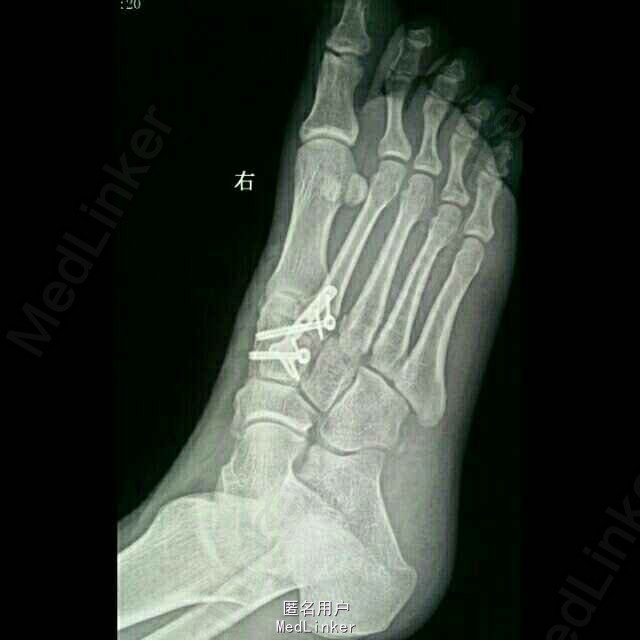

诊断:1.右足第2、3跖骨基底部骨折(Lisfranc损失) 2.右足内侧楔骨骨折 3.骰骨骨折 治疗:切开复位内固定

本例Lisfranc损伤涉及内侧柱和中间柱,中足稳定性破坏,足弓增宽,保守治疗效果很差,需采取内固定方法治疗。